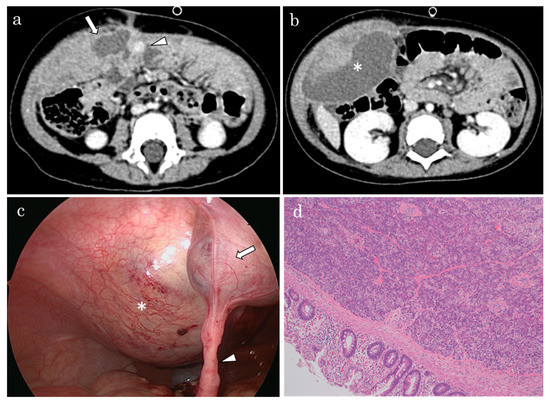

2. Case Report